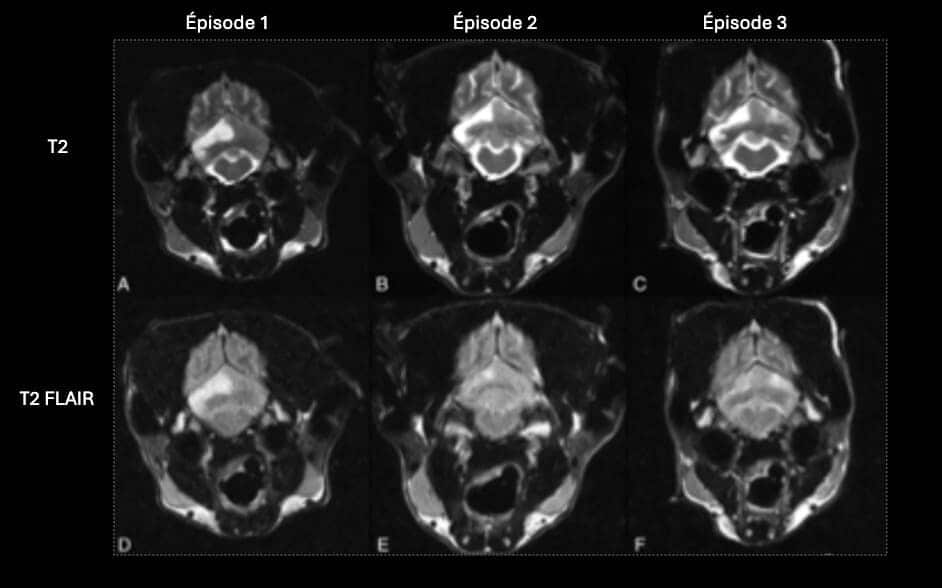

L’IRM est l’imagerie de choix pour ces lésions ischémiques. Les lésions aigues apparaissent hyperintenses sur les séquences T2 et T2 FLAIR, hypointense en pondération T1, et ne montrent pas de rehaussement. L’imagerie en diffusion permet une détection plus précoce de ces lésions. Elle permet également une estimation de l’âge de la lésion et de la taille du noyau infarcié. Les lésions aigues présentent une restriction du signal de diffusion, et apparaissent hyperintense sur la séquence DWI, et hypointenses sur la carte ADC. Les valeurs sur la séquence ADC sont diminuées pendant 4-5 jours, se normalisent entre 4 et 10 jours, et réaugmentent après 10 jours. Ces lésions ne créent pas d’effet de masse, sauf en cas d’œdème vasogénique associé, à son maximum 3-4 jours après l’apparition de la lésion. On peut parfois observer un rehaussement périphérique de la lésion pendant la phase de rupture de la barrière hématoméningée.

En phase chronique, le signal T2 reste stable, mais on observe une réduction progressive du signal en T2 FLAIR. Le signal est parfois mixte sur la séquence T2 FLAIR, en raison de la présence de zones hypointenses d’encéphalomalacie, et de zones hyperintenses de gliose. La taille des lésions diminue en phase chronique, avec atrophie du parenchyme cérébral. Le rehaussement éventuellement présent disparait lors de la restauration de la barrière hématoméningée.